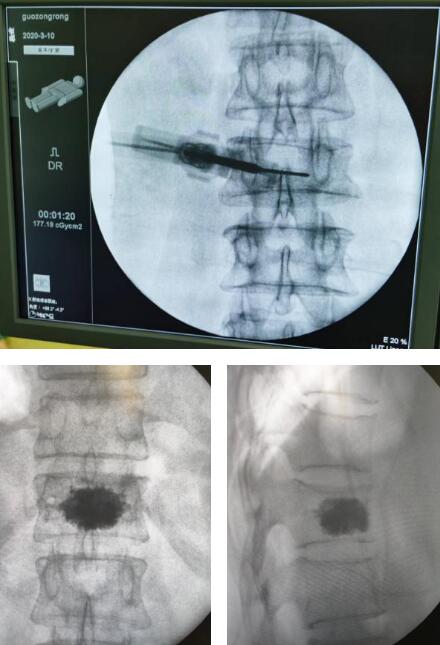

6月22日,孟大爷的椎体成形手术进行。手术医生先安装3D导航机器人示踪器,透视定位胸12椎体,行3D成像,模拟胸12左侧椎弓根穿刺,在定位点做一长约0.5厘米切口,通过导航机器人套筒于胸12左侧椎弓打入导针,直至到达椎体后1/4处,更换骨水泥工作套管,通过置入的骨水泥注入器在透视下缓慢注入填充约2ml骨水泥,待初步凝固后再次注入2ml骨水泥,确定椎体高度恢复且无明显骨水泥外溢,最后取出骨填充装置。手术不到1小时顺利结束。